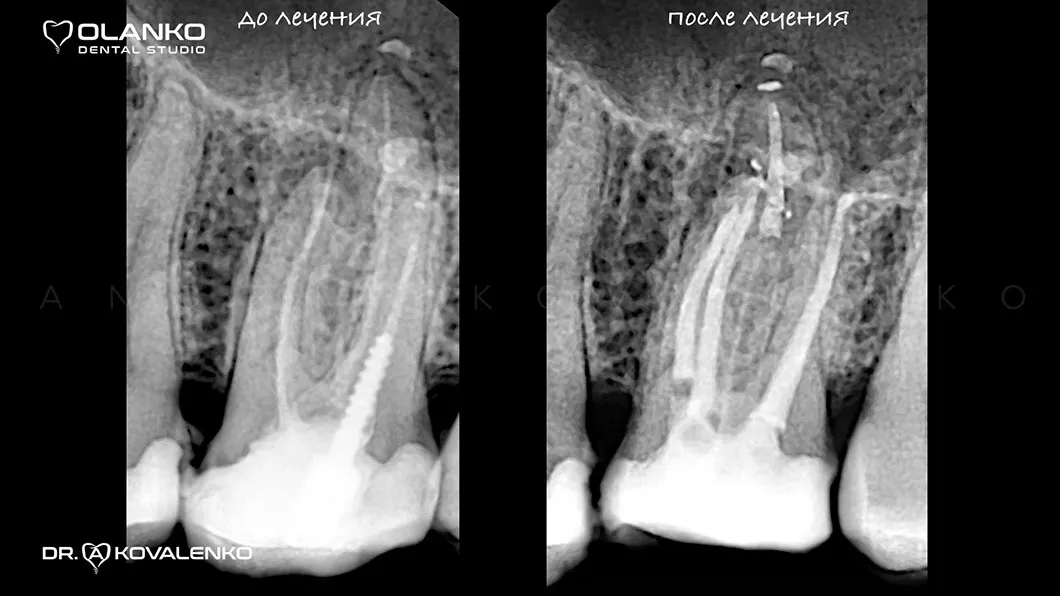

ВИДЕО ЛЕЧЕНИЯ КОРНЕВЫХ КАНАЛОВ ЗУБА ПОД МИКРОСКОПОМ С ПОСЛЕДУЮЩИМ ВОССТАНОВЛЕНИЕМ КЕРАМИЧЕСКОЙ КОРОНКОЙ

до

после

Лечение корневых каналов зуба с использованием микроскопа, на сегодняшний день, является золотым стандартом мировой стоматологической практики. Сложная система корневых каналов в зубе имеет очень малый диаметр и индивидуальную анатомию, поэтому врач, работающий без увеличения, не может качественно очистить и найти все корневые каналы на ощупь.

На примере перелечивания корневых каналов верхнего жевательного зуба

Мы имеем огромный клинический опыт лечения зубов со сложной анатомией (искривлёнными, склерозированными каналами), а также повторного перелечивания каналов с кистами, гранулемами, сломанными инструментами, с последующими отличными результатами заживления очагов хронического воспаления.